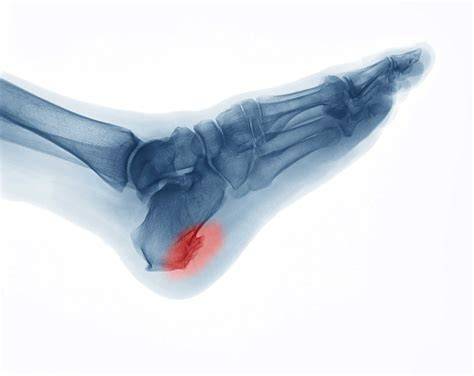

What is Ankle Bone Spur?

An ankle bone spur or osteophyte is a hard and smooth bump of extra bone that usually develops near joints. It is a bony growth formed on normal bone, as the body tries to repair itself by building extra bone. It is generally formed in response to constant pressure or stress over a long time.

X-rays: X-rays help to indicate bone spur formation and highlight the degeneration of the spinal cords. The X-ray also indicates the distance between bones.